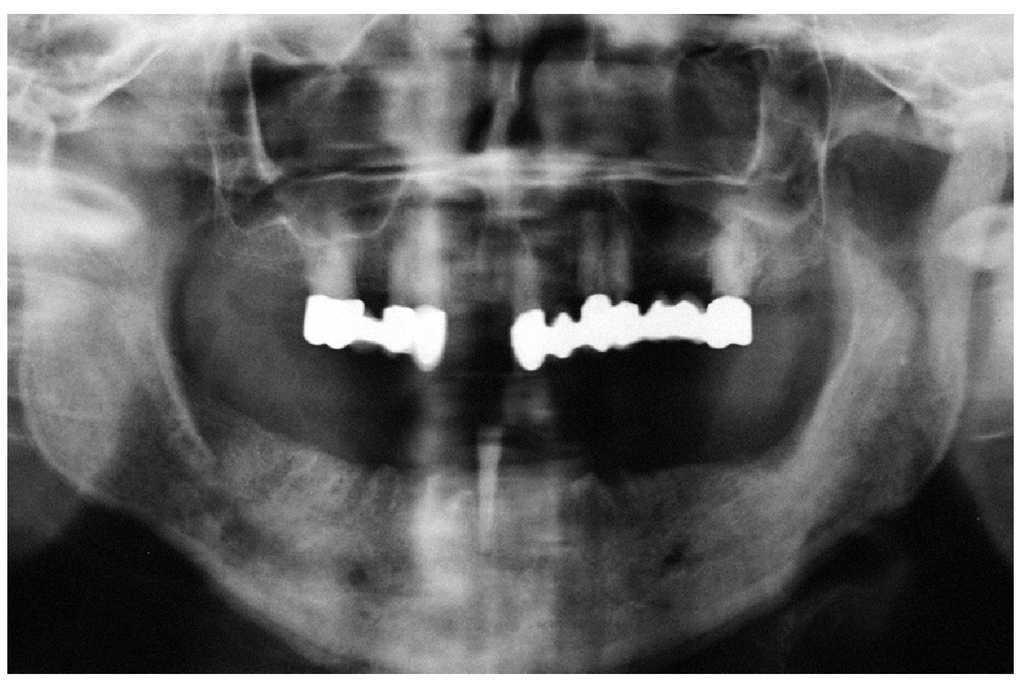

Figura 4c. La radiografía panorámica aporta pocos datos en contraste con el cuadro clínico florido. Además de una imagen radiolúcida difusa en el sector anteroinferior, se observan los alvéolos conservados, a pesar de que la extracción de los dientes se remonta a varios meses atrás. Llaman la atención la radiopacidad y el engrosamiento del periostio.

En las radiografías se aprecia a menudo la persistencia de las paredes corticales de los alvéolos después de las extracciones. Sin embargo, en la fase inicial las imágenes radiográficas a menudo no revelan alteraciones significativas a pesar de un cuadro clínico florido (figs. 5a a 5c). En una fase más avanzada se observan tanto imágenes radiolúcidas difusas como también imágenes radiopacas en las regiones óseas afectadas, pudiendo apreciarse en algunos casos un secuestro o fracturas óseas5.